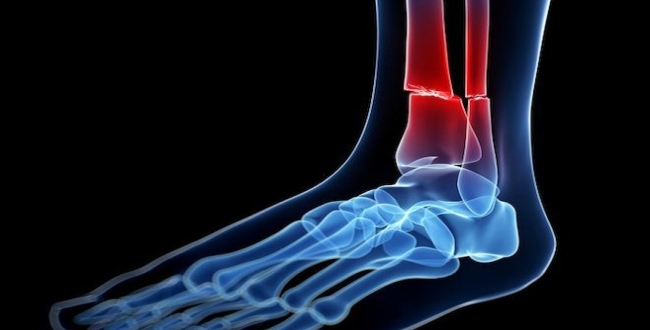

Compound Fracture

எலும்பு உடைந்து தோலை கிழித்து வெளியே தெரியும். இது மிகவும் ஆபத்தானது.

எலும்பு வளைந்த அல்லது தவறான வடிவம்

சில நேரங்களில் எலும்பு வெளியே தெரியும்